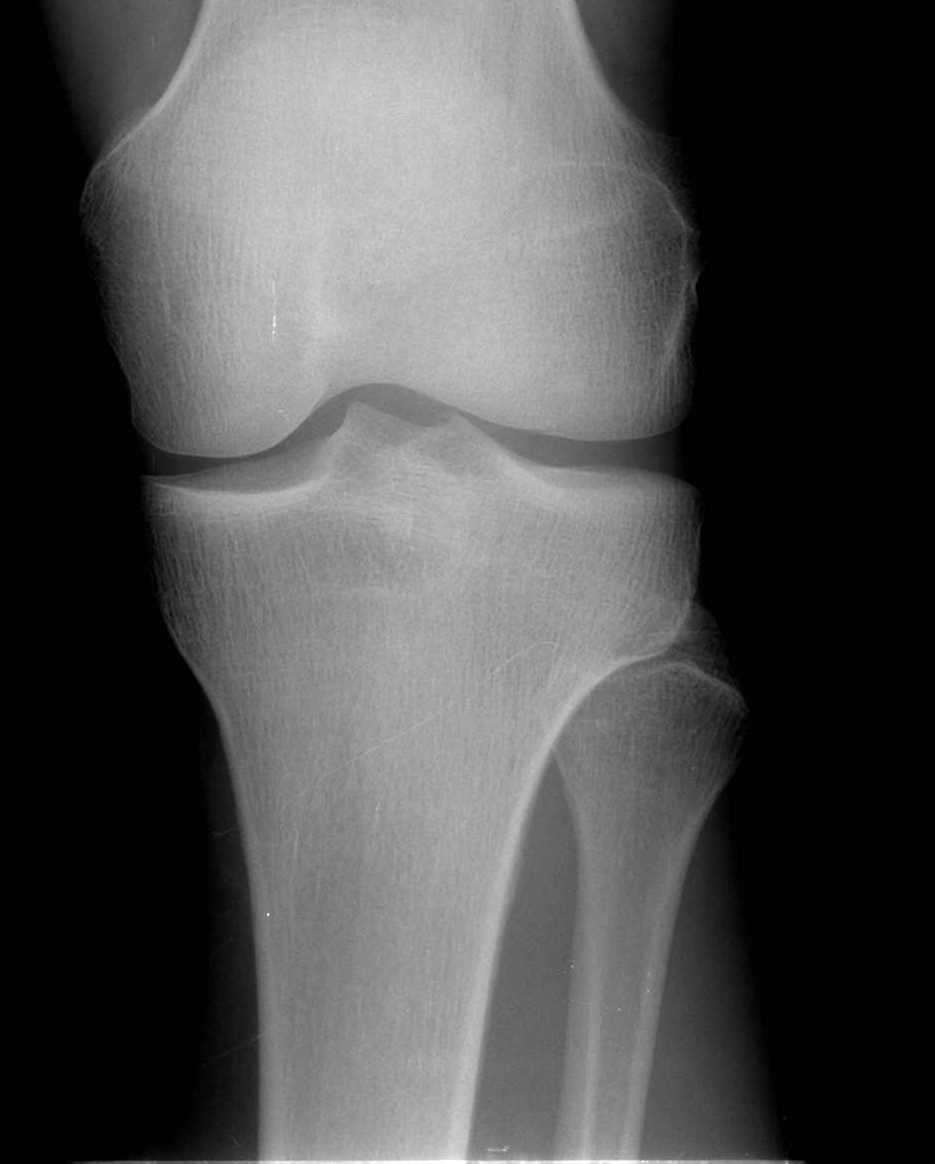

Добрый вечер уважаемые колеги. Проблема в следующем.Обратился пациент, возраст 26лет.

Травму левого коленного сустава отмечает около 2-х месяцев назад( при игре в футбол). За мед

помощью обратился не сразу, а как обратился, все консервативные мероприятия( мази, гели,

мумие, физиолечение) без эффекта. Сохраняются боли при нагрузке. Локально: отека

коленного сустава нет, выпота в суставе нет(и не было). Связочный аппарат коленного сустава

стабилен. Симптомы повреждения внутрисуставных структур отр(-). Пальпаторно умеренная

болезненность в проекции головки м/берцовой кости, а при сравнительном исследовании

определяется подвижность головки м/берцовой кости по отношению к тибии с больной

стороны.Ds: Застарелый разрыв проксимального межберцового синдесмоза левой

голени.Хотелось бы посоветоваться, кто сталкивался с такой проблемой как лучше помочь

больному.наш вариант лечения:открыто выделить место вырезки б/берцовой кости,установка

м/берцовой кости на место и фиксация берцовых костей винтом или болтом стяжкой ч/з область

шейки м/берцовой кости, дополнительно в ходе доступа выделить м/берцовый нерв для

спокойной работы в этой зоне. Жду ваших советов.С уважением Андрей